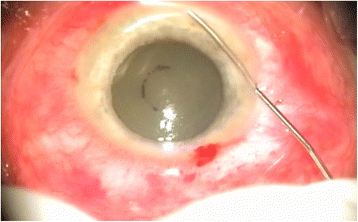

Інфузія ванкоміцину під час хірургічного лікування пост-травматичного ендофтальміту